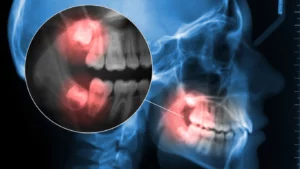

Understanding what constitutes a dental emergency can save you from severe pain, infections, and costly treatments. This emergency dentist overview: